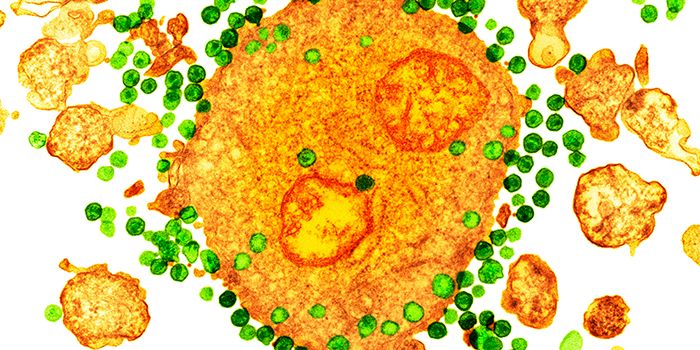

AUG 24, 2020ImmunologyOnce in the body, HIV tracks down T cells that bear the CD4 receptor. It attaches to these immune cells, fusing itself w ...